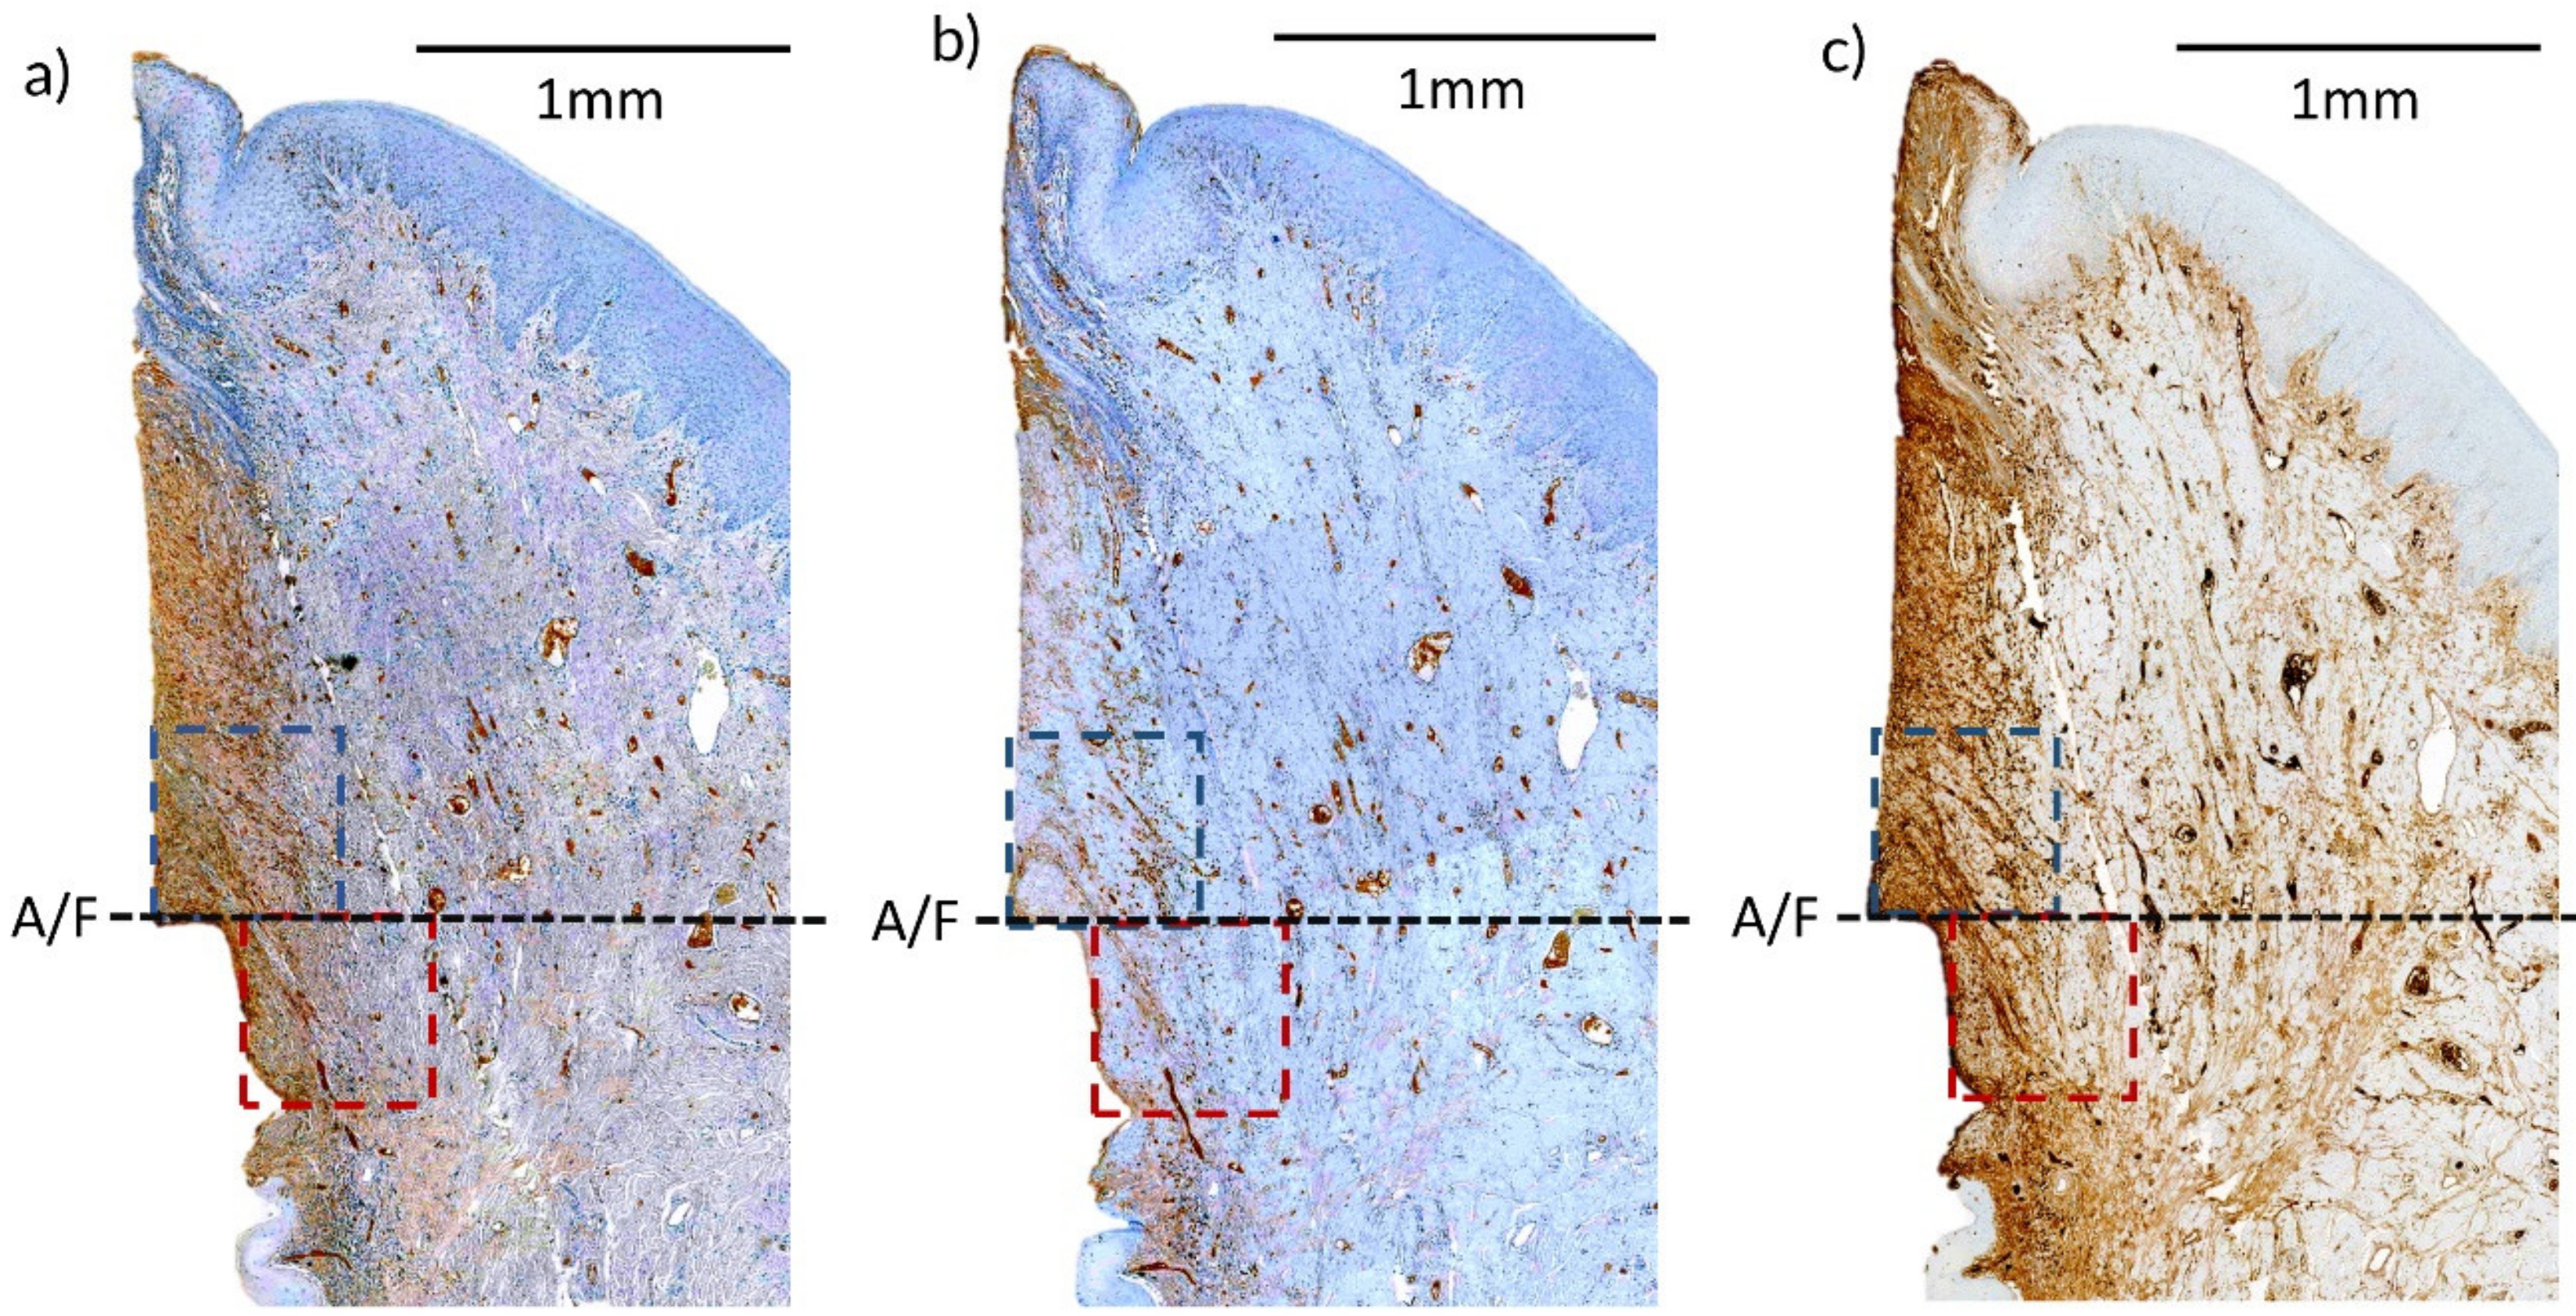

2.3.6. Histological Preparation and Outcomes

3.4. IHC Cell Marker Analysis